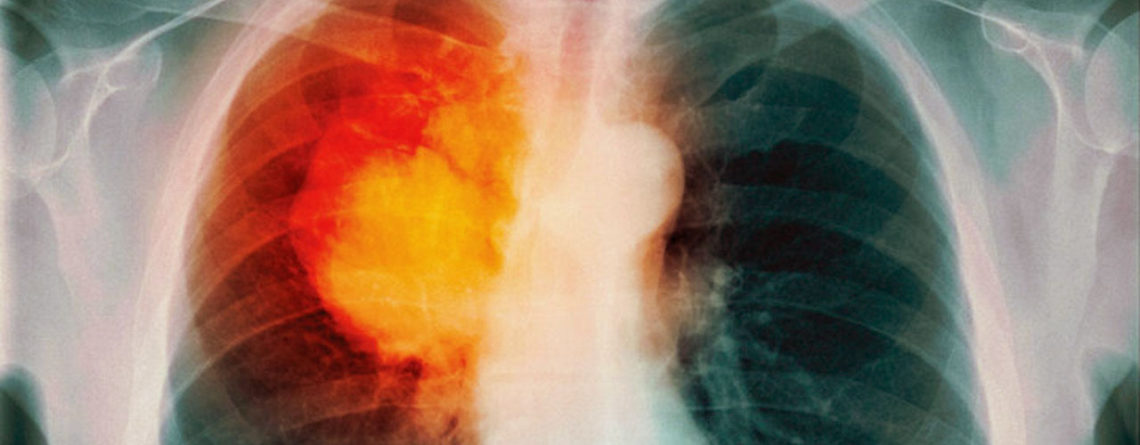

Химиотерапия – тяжелое, но эффективное средство лечения онкологической патологии. Многих пациентов беспокоят осложнения после химиотерапии при раке легкого, и неудивительно: во время курса лечения пациенты могут ощущать слабость, головную боль, их беспокоят общие и частные симптомы.

Во время химиотерапии происходит торможение роста злокачественных очагов. Пациенты с раком легких после химиотерапии отмечают облегчение в «онкологическом плане», то есть, их перестают беспокоить симптомы рака легких, но могут появляться побочные эффекты проведенного лечения.

Высокая токсичность, значительные дозы препаратов, вводимых во время курса, приводят к системным нарушениям работы организма.

Часто у пациентов возникают различные симптомы после химиотерапии рака легких.

Страдает пищеварительная система: появляются диарея или запор в зависимости от реакции организма на проводимое лечение.

Нередко пациентов беспокоят диспепсические расстройства: тошнота, рвота и нарушение переваривания пищи.

Общие побочные симптомы касаются слабости, усталости, головной боли.

Иногда проявления касаются и анализов крови: снижаются показатели лейкоцитов, эритроцитов и тромбоцитов, что сказывается на иммунном статусе организма, может возникать анемия и нарушение свертываемости крови.